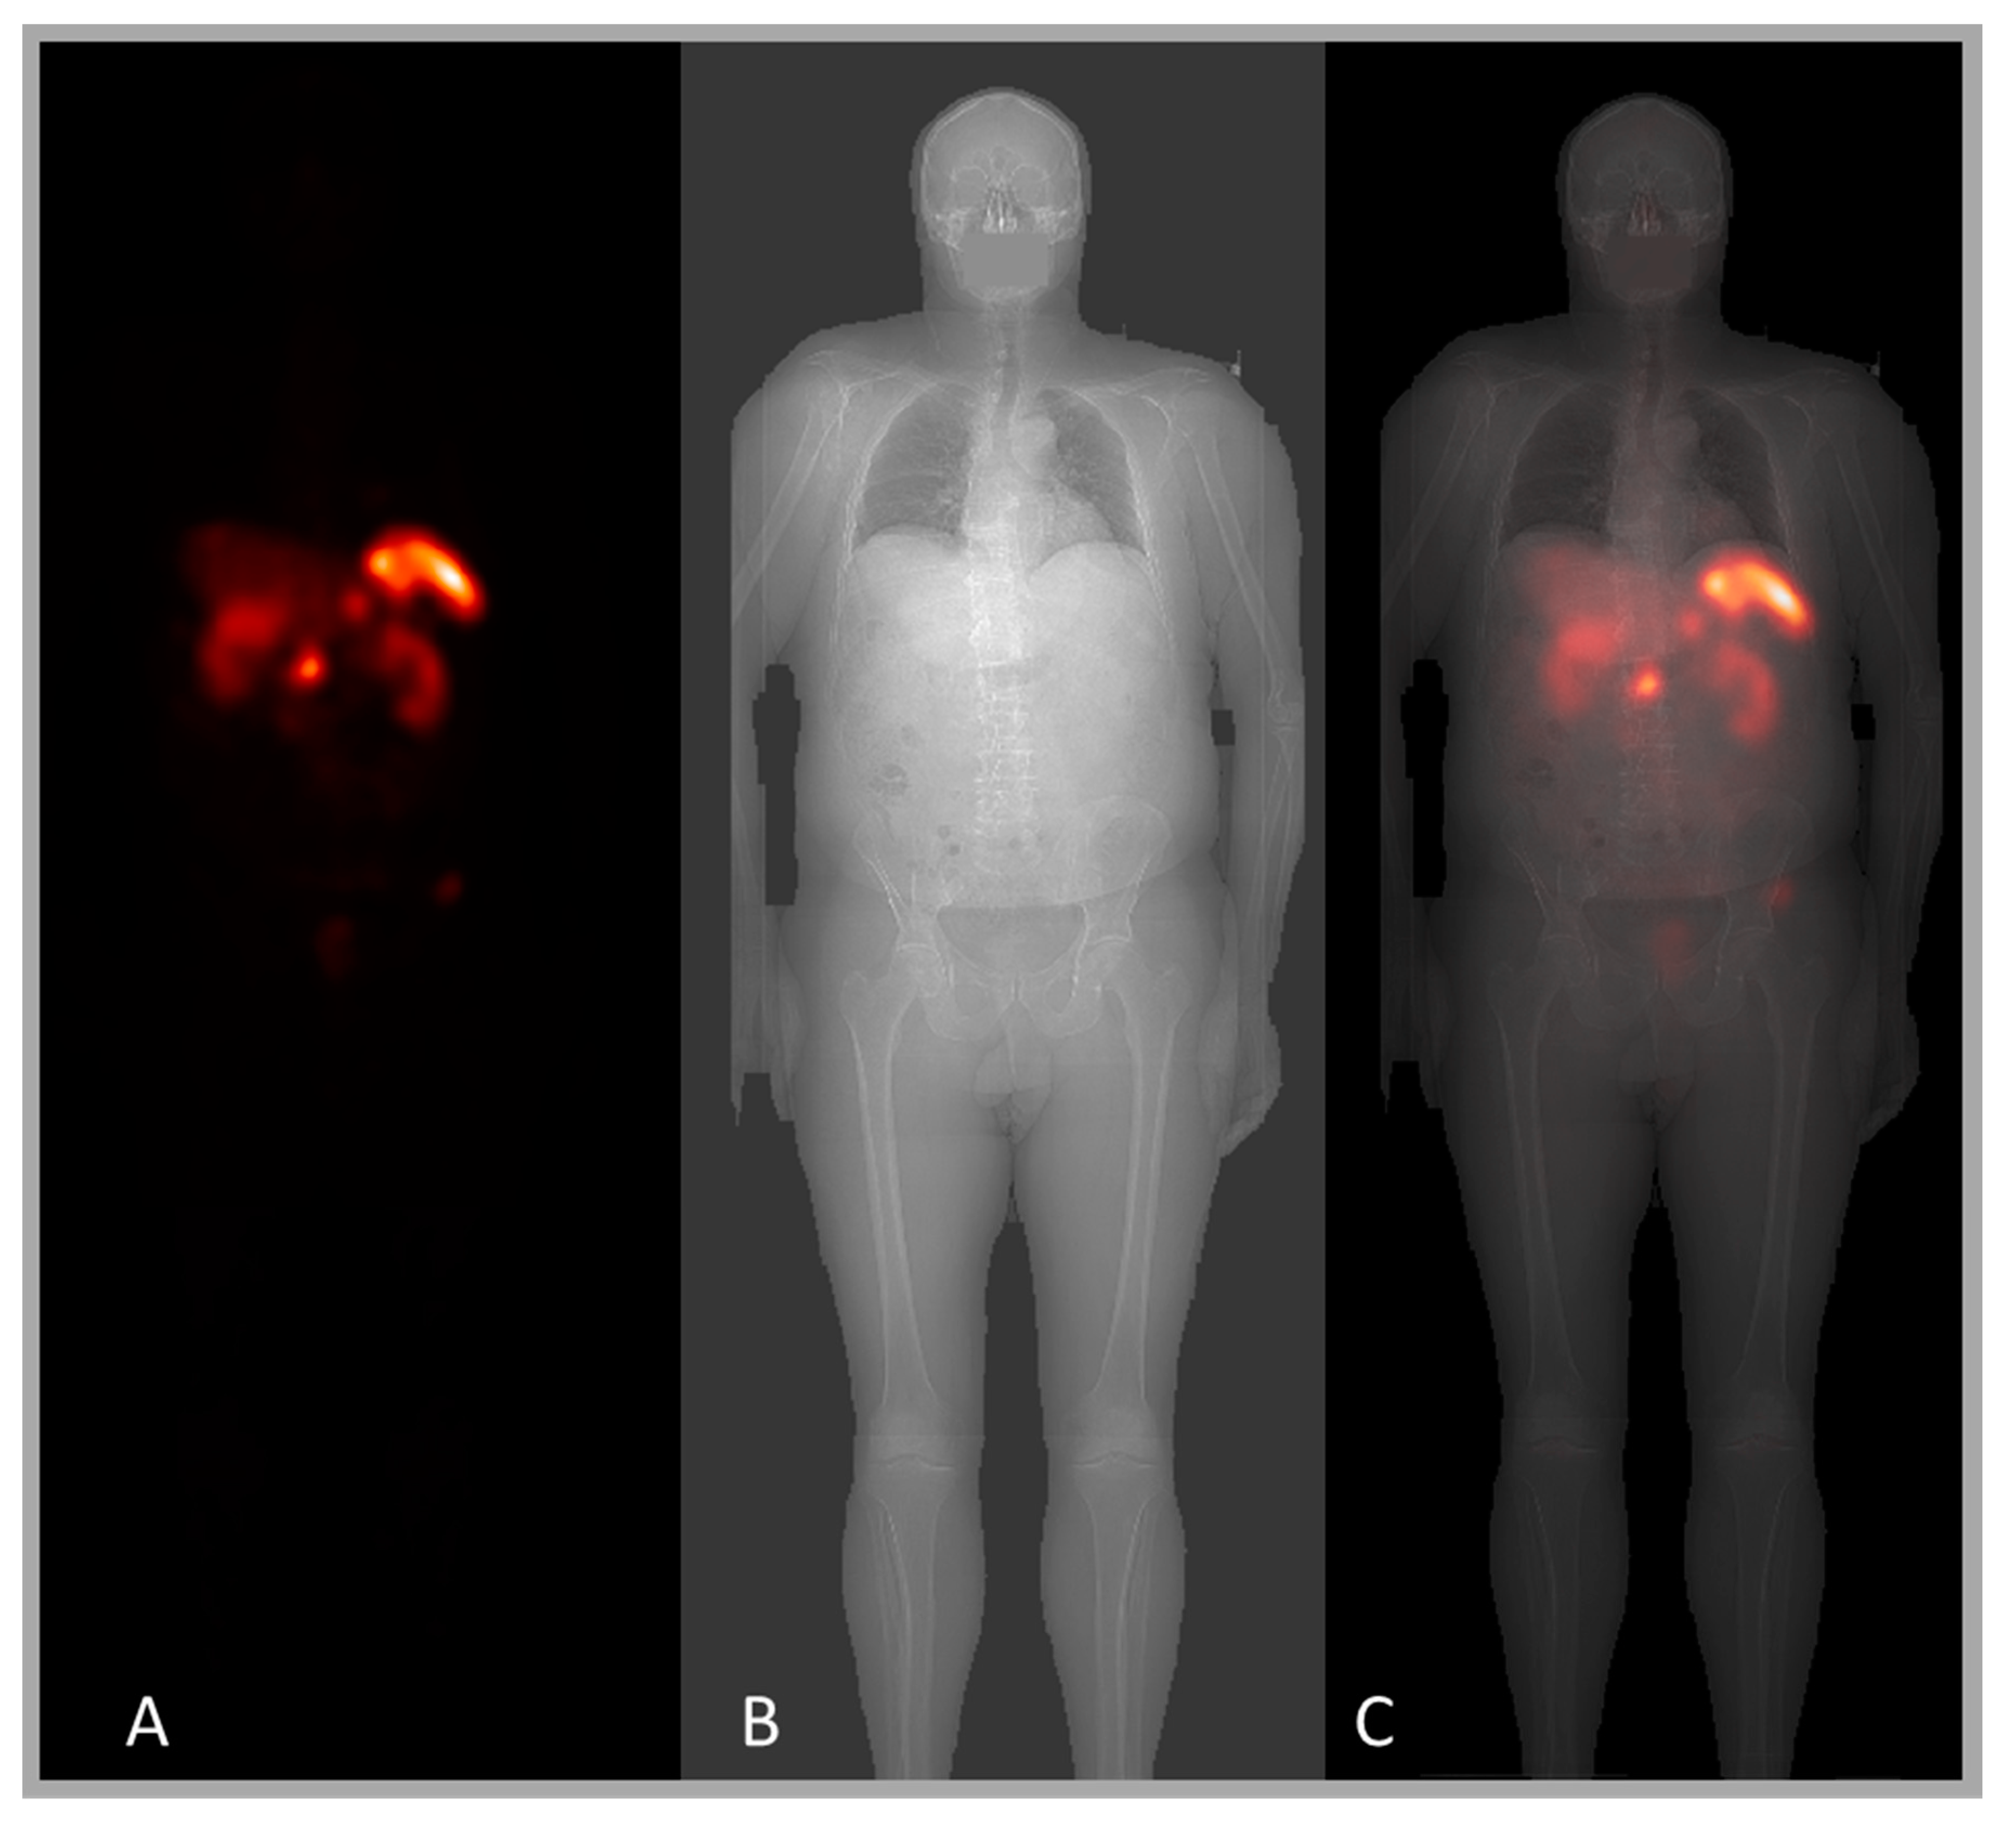

5. Planar-Image Based Activity Quantification

5.1. Conjugate-View Principles

5.2. Attenuation Correction Based on X-Ray Scout

5.3. Scatter Compensation Based on X-Ray Scout

5.4. ROI Definitions Using the X-Ray Scout

8.1. Registration of Planar Whole-Body Images and X-Ray Scout